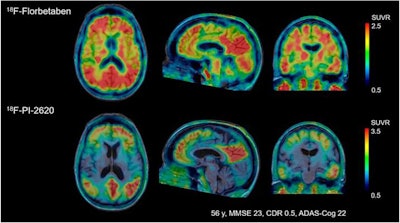

Their visual analyses of the resulting tau PET images showed F-18-PI-2620 uptake in the cortical regions of patients with Alzheimer's disease, particularly in the temporal and parietal lobes, precuneus, and posterior cingulate cortex. By comparison, there was no such uptake in cerebral brain regions of healthy control subjects, which allowed for their differentiation from patients with Alzheimer's disease, the authors noted.

This past January, LMI (formerly known as Piramal Imaging) unveiled encouraging results on studies of its PET neuroimaging tracers, which included the combination of its own florbetaben F-18 injection (Neuraceq) with F-18-PI-2620 to detect tau pathology in patients with Alzheimer's disease, as well as people with progressive supranuclear palsy and corticobasal syndrome.